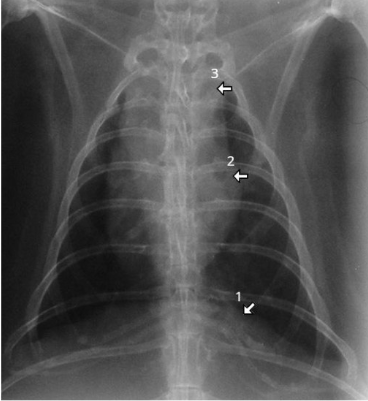

What species and what are the numbers

rabbit

1 = diaphragm 2 = cardiac silhouette

= mediastinum which is larger in rabbits